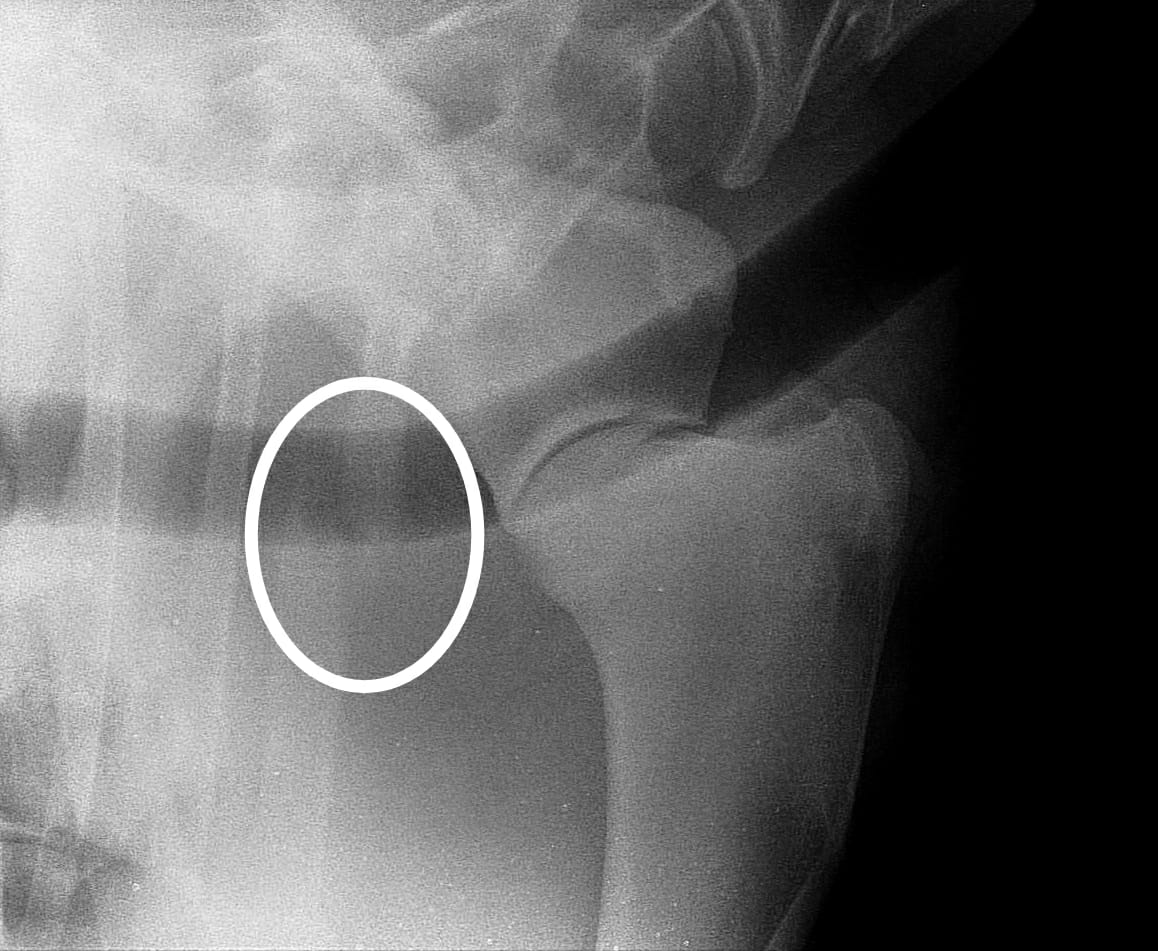

Dado que son síntomas inespecíficos de otras patologías, el diagnóstico definitivo de una fractura de costilla requiere una ecografía, radiografía de tórax o incluso una gammagrafía, donde las fracturas muestran mayor captación de radiofármaco dentro de las 24-72 horas posteriores a la lesión, lo que lo convierte en un método diagnóstico altamente sensible en la etapa aguda de la enfermedad en comparación con la radiografía que puede no observarse alteración hasta pasados 7-10 días del acontecimiento traumático, a menos que sea una fractura desplazada.

La ecografía resulta un método diagnóstico de gran utilidad tanto en la fase aguda de la enfermedad, como posteriormente para el control de la cicatrización, facilitando la identificación de los casos que no evolucionan correctamente y requieren intervención quirúrgica.